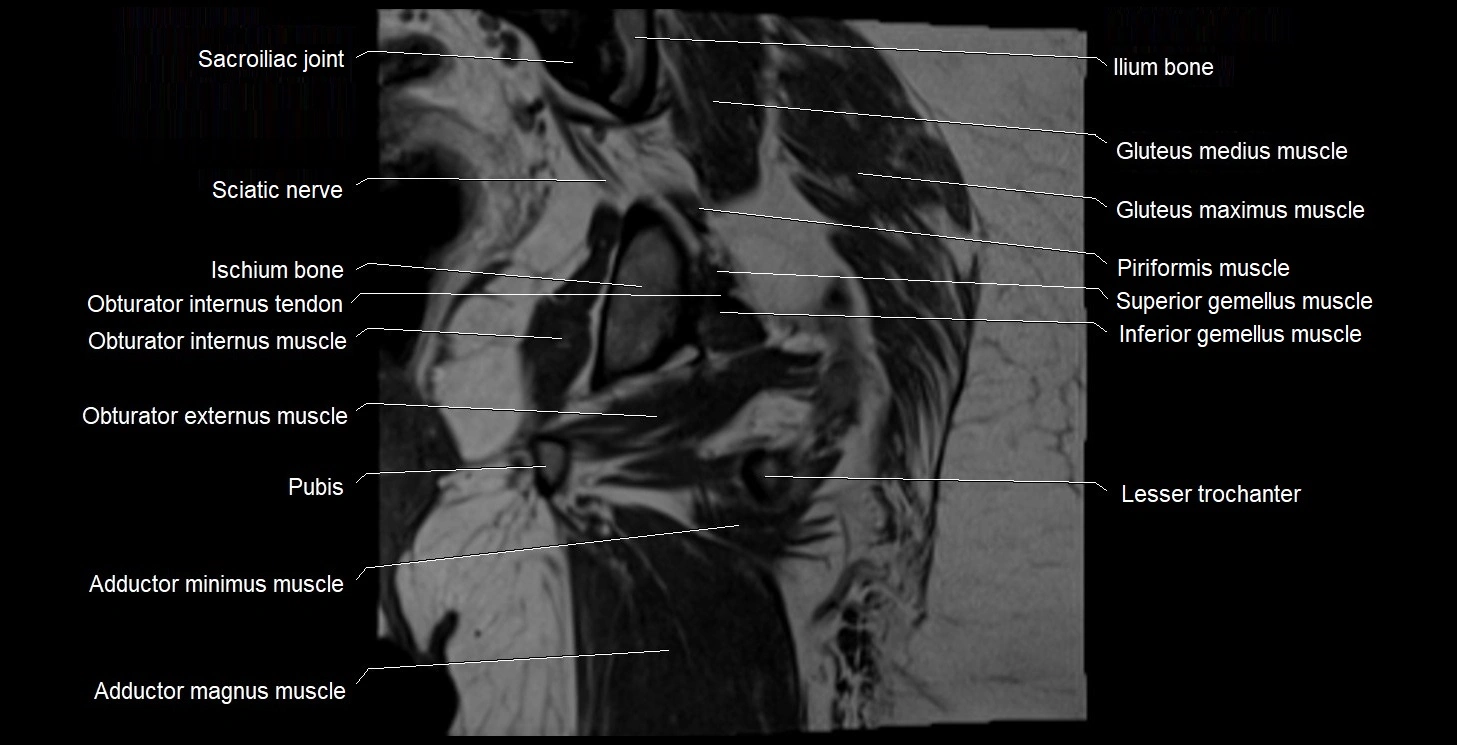

- Adductor magnus muscle

- Adductor minimus muscle

- Inferior gemellus muscle

- Ischium bone

- Lesser trochanter

- Obturator externus muscle

- Obturator internus muscle

- Obturator internus tendon

- Quadratus femoris muscle

- Sacroiliac joint

- Superior gemellus muscle